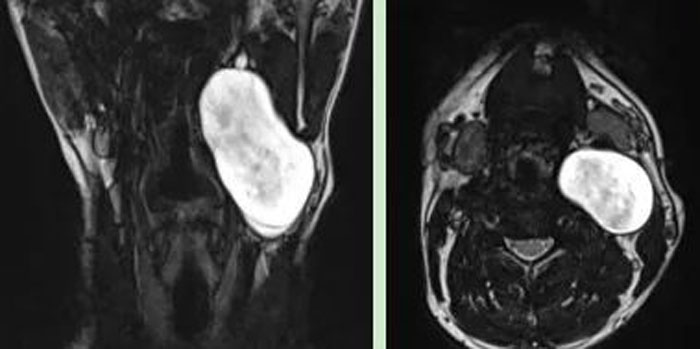

患者,男,26歲,2年前發(fā)現(xiàn)頸部左側(cè)腫物,逐漸增大,來(lái)我院就診。彩超示:左側(cè)頸部探及約5.0×4.3cm低回聲團(tuán)塊;頸部MRI示:左側(cè)頸部囊性占位,考慮良性病灶,大小約3.5×5.1×7.2cm。

患者年紀(jì)輕,病情復(fù)雜,經(jīng)充分準(zhǔn)備后,在牛善利主任指導(dǎo)下,牛傳貴副主任醫(yī)師、步明強(qiáng)副主任在全麻下實(shí)施頸部腫物切除術(shù)。術(shù)中見(jiàn)腫物位于頸動(dòng)脈鞘內(nèi),將頸內(nèi)靜脈及迷走神經(jīng)擠向外側(cè),將頸內(nèi)、外動(dòng)脈擠向內(nèi)側(cè),腫物下緣至環(huán)狀軟骨水平,上緣至二腹肌后腹深面向上近顱底處。此次手術(shù)難度大,手術(shù)操作復(fù)雜,手術(shù)風(fēng)險(xiǎn)大,技術(shù)要求高,在手術(shù)室李蘊(yùn)護(hù)士長(zhǎng)、張建永護(hù)士長(zhǎng)、楊凌主管護(hù)師及麻醉科鄧燕副主任醫(yī)師密切合作下,手術(shù)順利完成。病理參考免疫組化報(bào)告神經(jīng)纖維瘤。術(shù)后患者恢復(fù)良好,已出院。(耳鼻咽喉科)